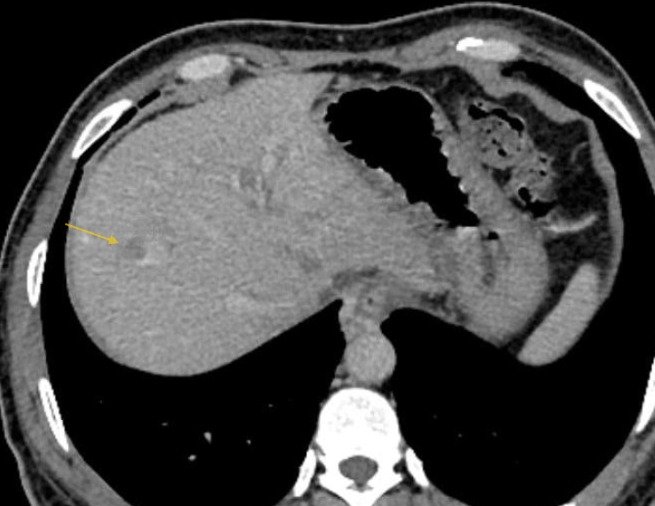

Minimally invasive treatment for liver cancers- TACE, Ablation and embolization

Tumor ablation, embolization , biopsy and FNAC. Palliation

Organ biopsy-CT /USG guided, FNAC, Pigtail and collection/fluid tapping.